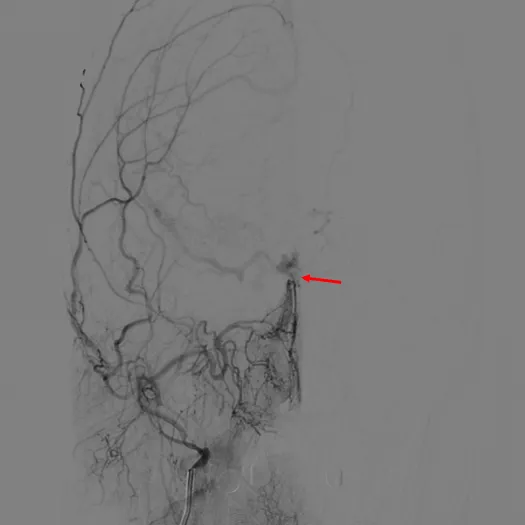

右颈内造影

经右眼动脉入路工作角度

经右眼动脉工作路径

SONIC微导管路径

SONIC微导管到位后手推造影确认

注胶

确认瘘口消失-右侧

确认瘘口消失-左侧

SONIC微导管到位较深,注胶时可采用楔入技术,Onyx胶基本未反流,头端无粘管, SONIC微导管头端未解脱即顺利拔管